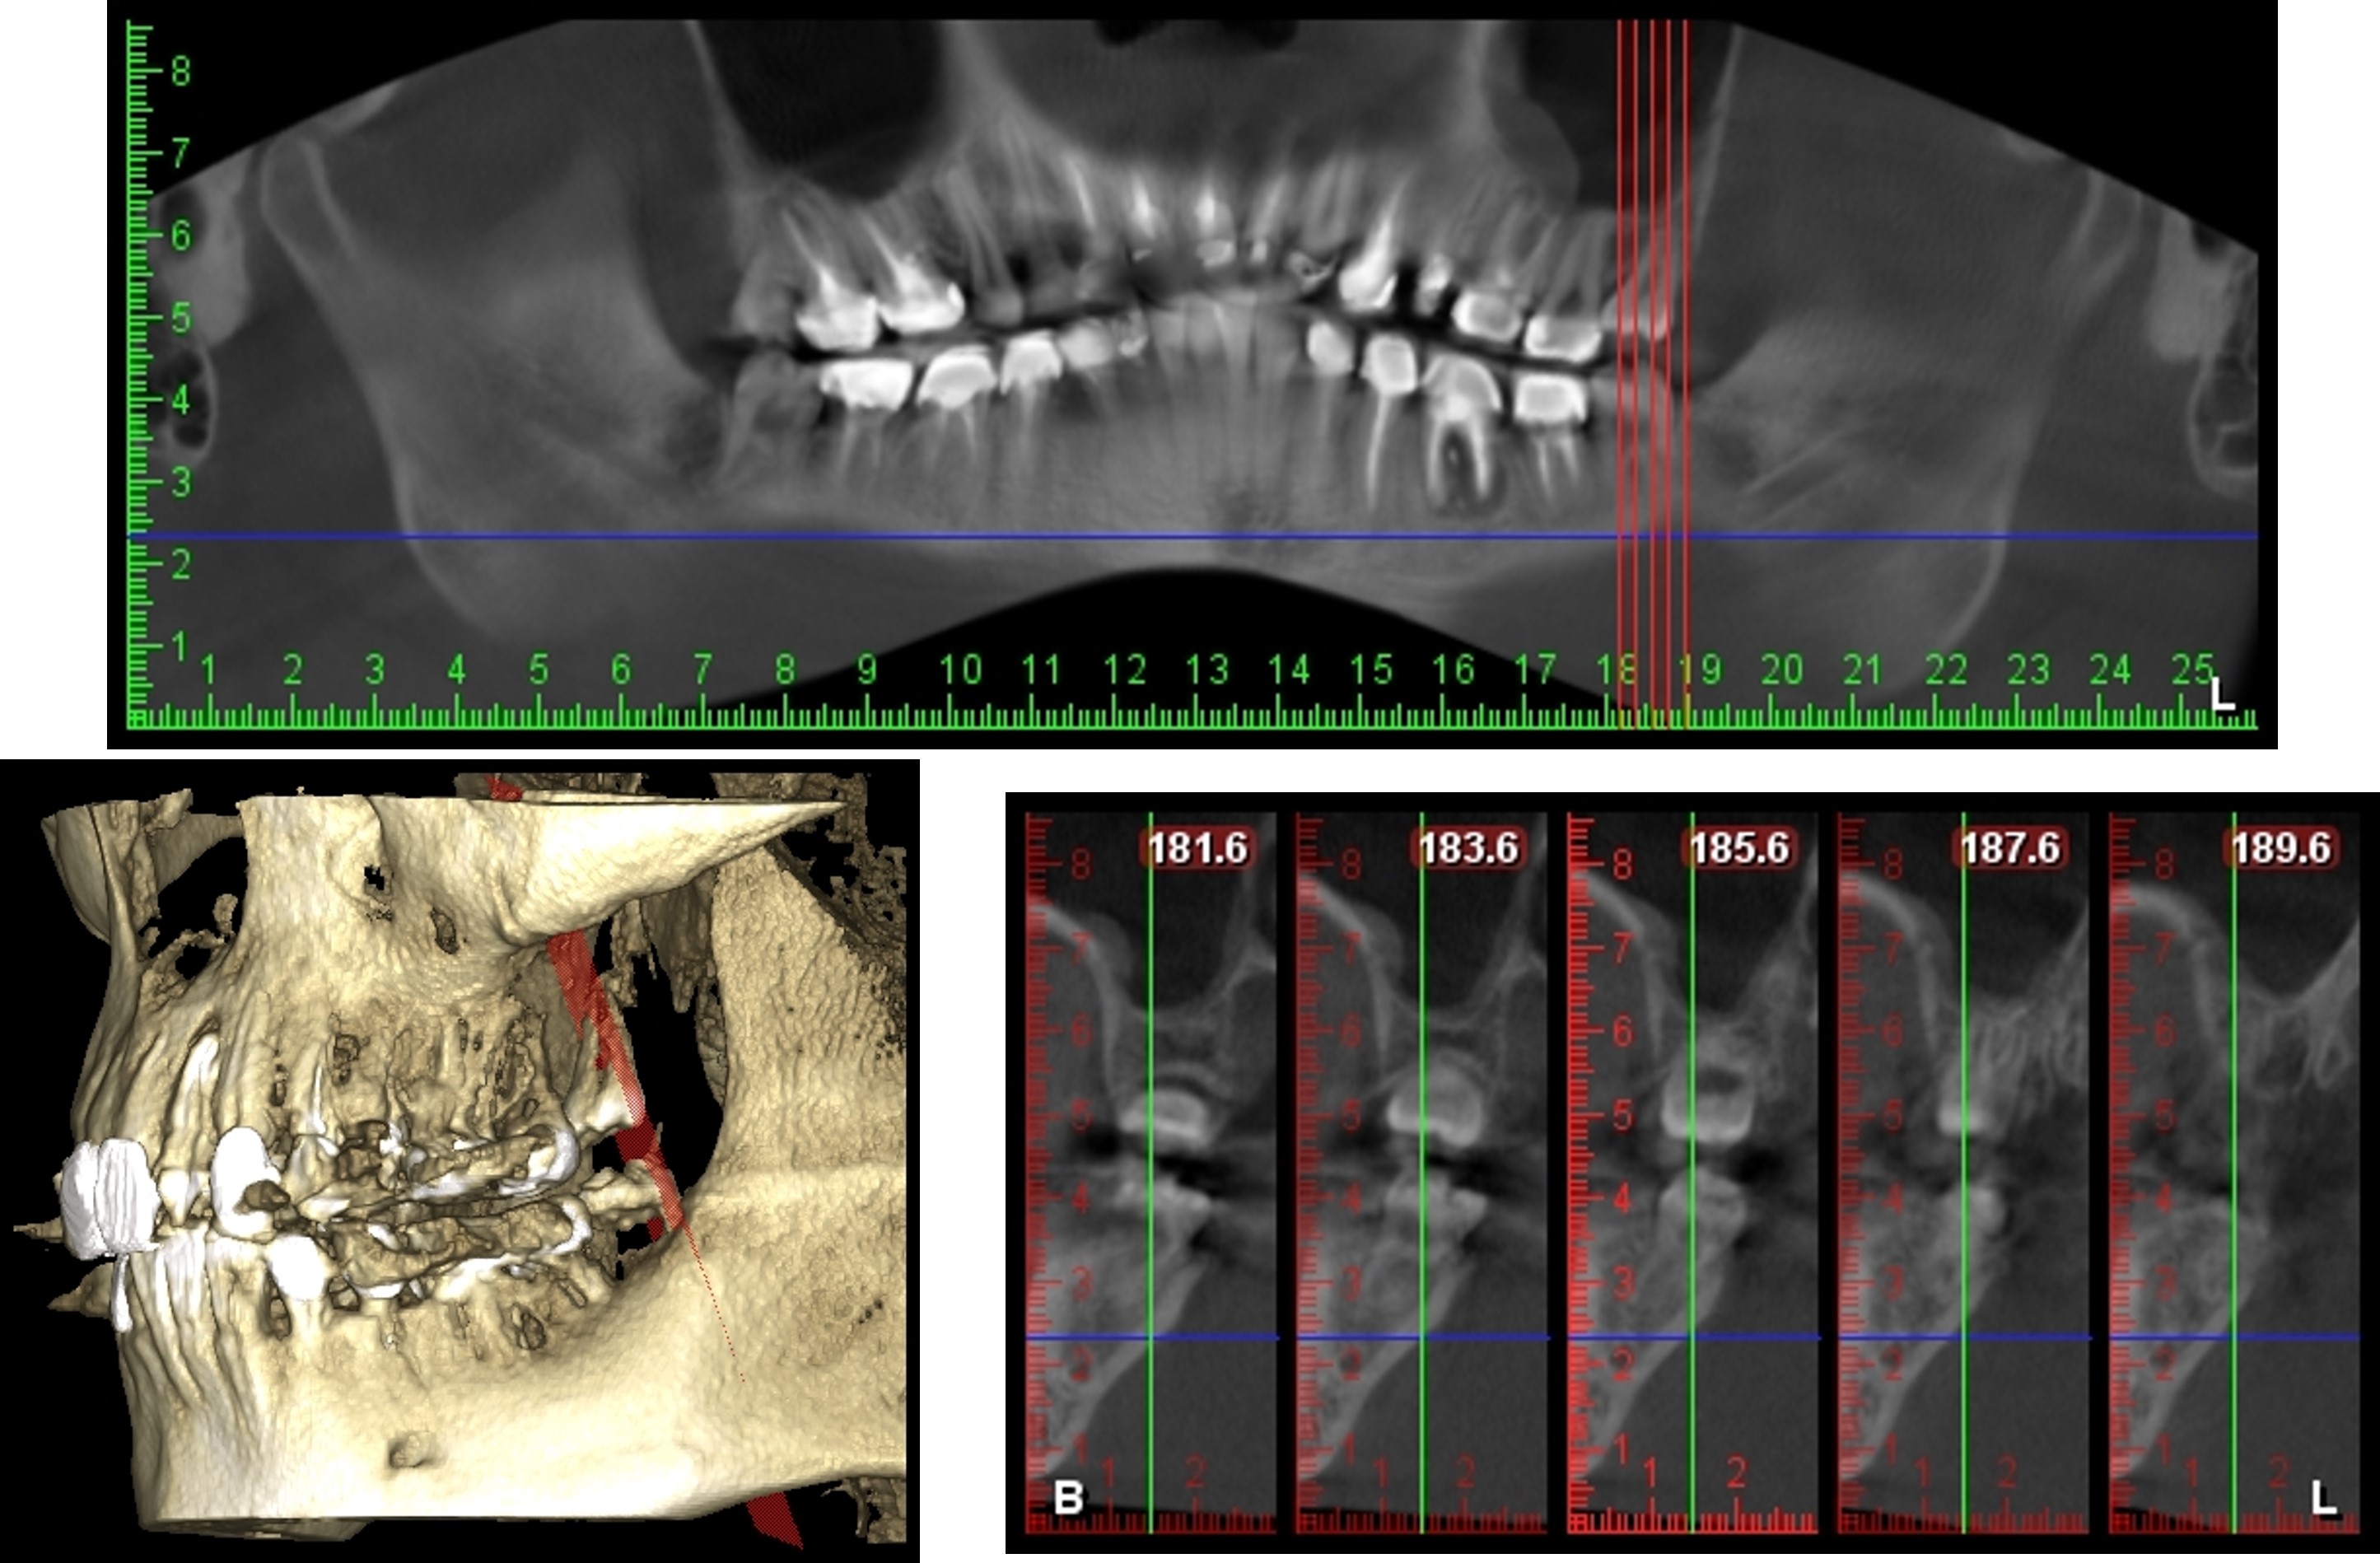

牙科專用的3D電腦斷層攝影;與傳統醫療電腦斷層相比較,輻射劑量只有一般電腦斷層的1/50;切片厚度一般醫療電腦斷層是2.0公厘,牙科3D電腦斷層則只有0.1公厘,就診當天馬上拍攝電腦斷層,馬上獲得立體影像。

電腦斷層顯示下齒槽神經距離遠